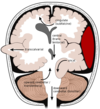

motor speech area located on left hemisphere (dominant side)

Broca’s area

- comprehension okay, repetitive of words difficulty.

Area on dominant side involved with understanding language.

Symptoms of Wernicke’s aphasia are.. (30

Wernicke’s area

symptoms; profound word-finding difficulty,

impaired repetition of words

profound loss of comprehension